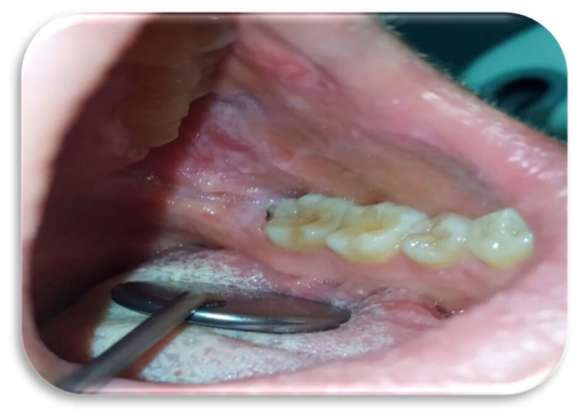

Sia sui margini linguali che sulle mucose geniene erano presenti, inoltre, segni di morsicatio buccarum e linea alba (Figure 3 e 4).

Al quarto giorno di applicazione, la paziente riportava un notevole miglioramento sintomatologico. A sette giorni c’era stata una regressione completa delle lesioni (Figure 5-6), con mucosa integra e normocromatica dove residuava linea alba a livello genieno e linguale (Figure 7-8), per la quale era stato consigliato alla paziente l’uso di un bite inferiore in resina morbida per evitare ulteriori traumi ai tessuti molli.